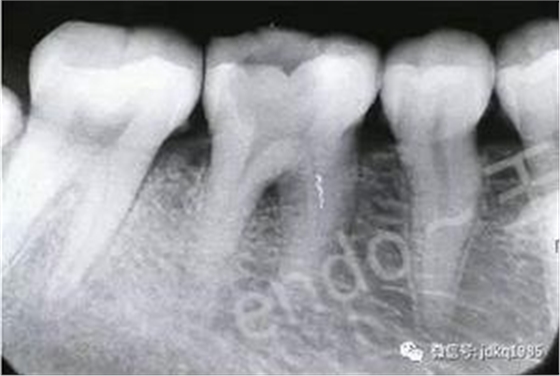

臨床病例報告:患者為30歲女性,因后牙自發(fā)性疼痛于當(dāng)?shù)蒯t(yī)院行“根管治療”,治療過程中出現(xiàn)“斷針”,建議轉(zhuǎn)診,遂來我院就診。X線檢查可見46近中根管中上段約3mm的高密度影像,其余根管內(nèi)未見充填影像,根尖區(qū)見密度減低透射影。由于患者存在根尖病變,且分離器械位于根管中上段,因此我們給患者擬定了根管內(nèi)分離器械取出的治療方案。

術(shù)前X線片可見近中根管內(nèi)分離器械